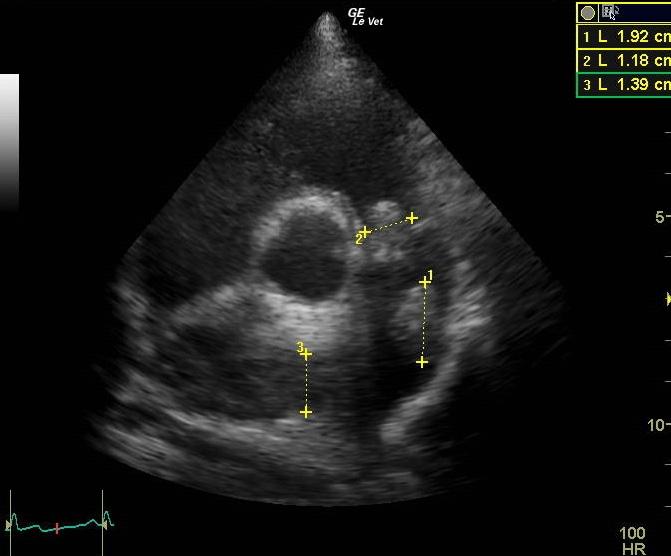

An 11-year-old MN Golden retriever was presented for evaluation due to two episodes of collapse and cyanosis. Additional history was that the patient was more lethargic than usual. Cardiac auscultation did not reveal any abnormalities and blood pressure was normal. Survey radiographs showed a mildly enlarged cardiac silhouette (VHS 11), prominent right ventricle, normal left atrial, and a normal lung pattern.